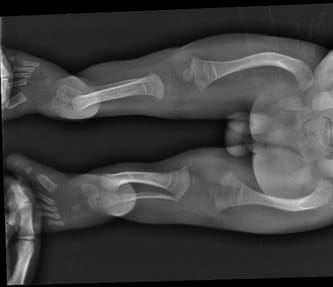

Adam was born on the seventh of October and despite the black visions of doctors he survived more than a few short moments on this Earth. Despite the doctors still strongly claimed that he suffer from osteogenesis imperfecta, we stubbornly proved them that they were wrong. And although they warned us not to hug him, carry on a wooden board, and not to rehabilitate him, groping and guided by our own intuition, we overcame the fear of illness and day by day, from week to week, we were more and more courageous in his care realizing that Adam is not a fragile human being, but a strong and valiant young man, on whom an unjust sentence was given. Our conviction was confirmed by genetic tests that ruled out the brittle bones. Looking for the best specialists in the field of orthopedics, we found Dr. Paley, who was able to correctly diagnose Adam's problem. His legs were never broken but only distorted. An ultrasound picture of pregnancy, as well as X-ray examination, gave the wrong impression of bone after fracture.

Adaś once again proved that he ia a real warrior and began to walk by himself. However, his legs are very curved in many places. Adaś needs a series of operations that will enable him to walk properly, avoid dislocating hips and joints and improve the comfort of his life. His disorder is extremely rare and the series of reconstructions is needed (including straightening femurs, bone of the lower leg, feet reconstruction, hip correction and many other procedures on the so-called soft tissues). After many researches, fate has once again put on our way to Dr. Paley who has his clinic in Florida. The doctor undertook the treatment of Adam to minimize the amount of surgery and thus reduce the amount of pain and suffering to the child. What's more, in our case, he agreed to perform operations in Poland. It is a great chance for us to ensure our son's proper development and in and socializing his peers.